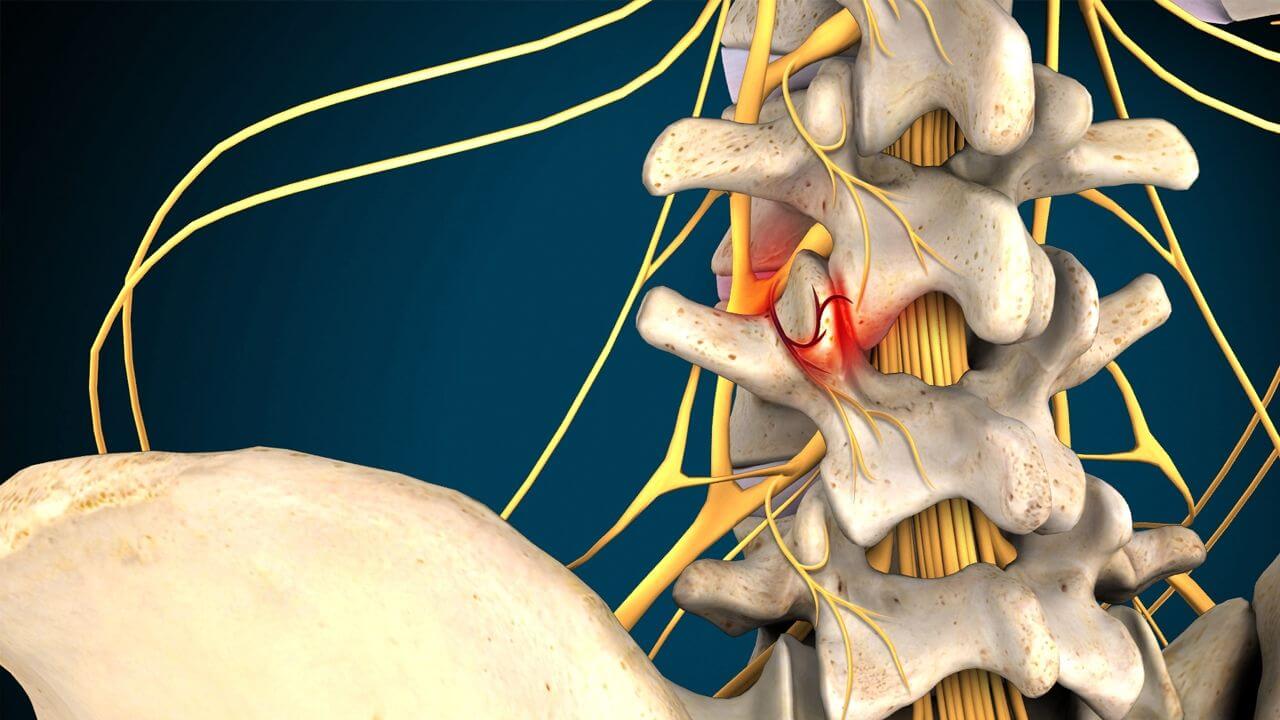

Остеоартрит фасеточных суставов: медицинские снимки и схемы